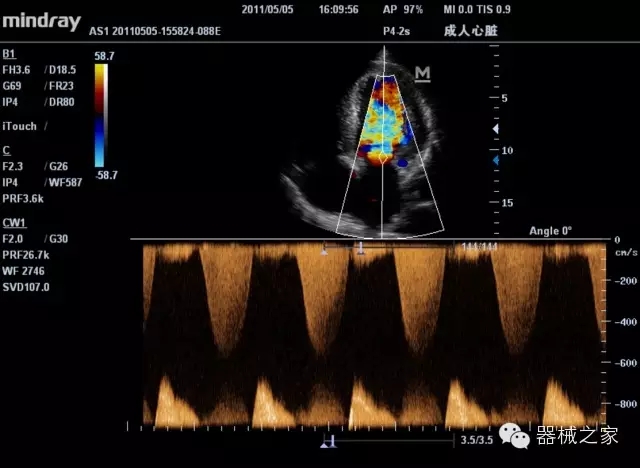

頸動(dòng)脈頻譜

臨床圖片賞析